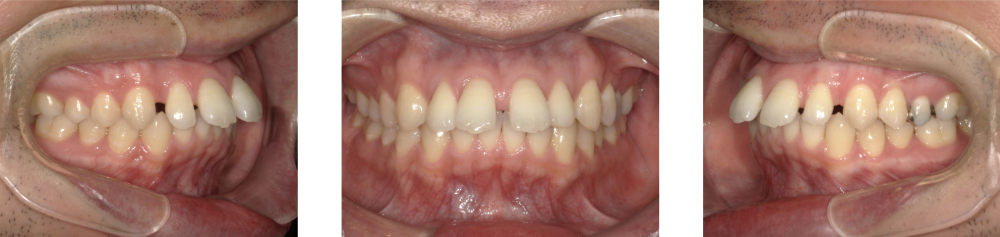

Before Photo

Before

主訴

上の前歯の隙間が気になる。

治療期間

2年1か月

料金

相談料0円、検査料33,000円、動的矯正治療費990,000円、保定装置料5,500円x2枚(必要枚数)

治療概要

上の前歯に隙間があるため、前歯を後退させながら、隙間を閉じた。

この時、上下の前歯が強く干渉すると再度隙間が空いてくるため、上下前歯の咬合が強くならないように配列した。

矯正での歯の移動のリスクとして歯根吸収、歯肉退縮、歯髄怪死が考えられます。

保定装置の装置を怠ると隙間が生じてくる可能性があります。